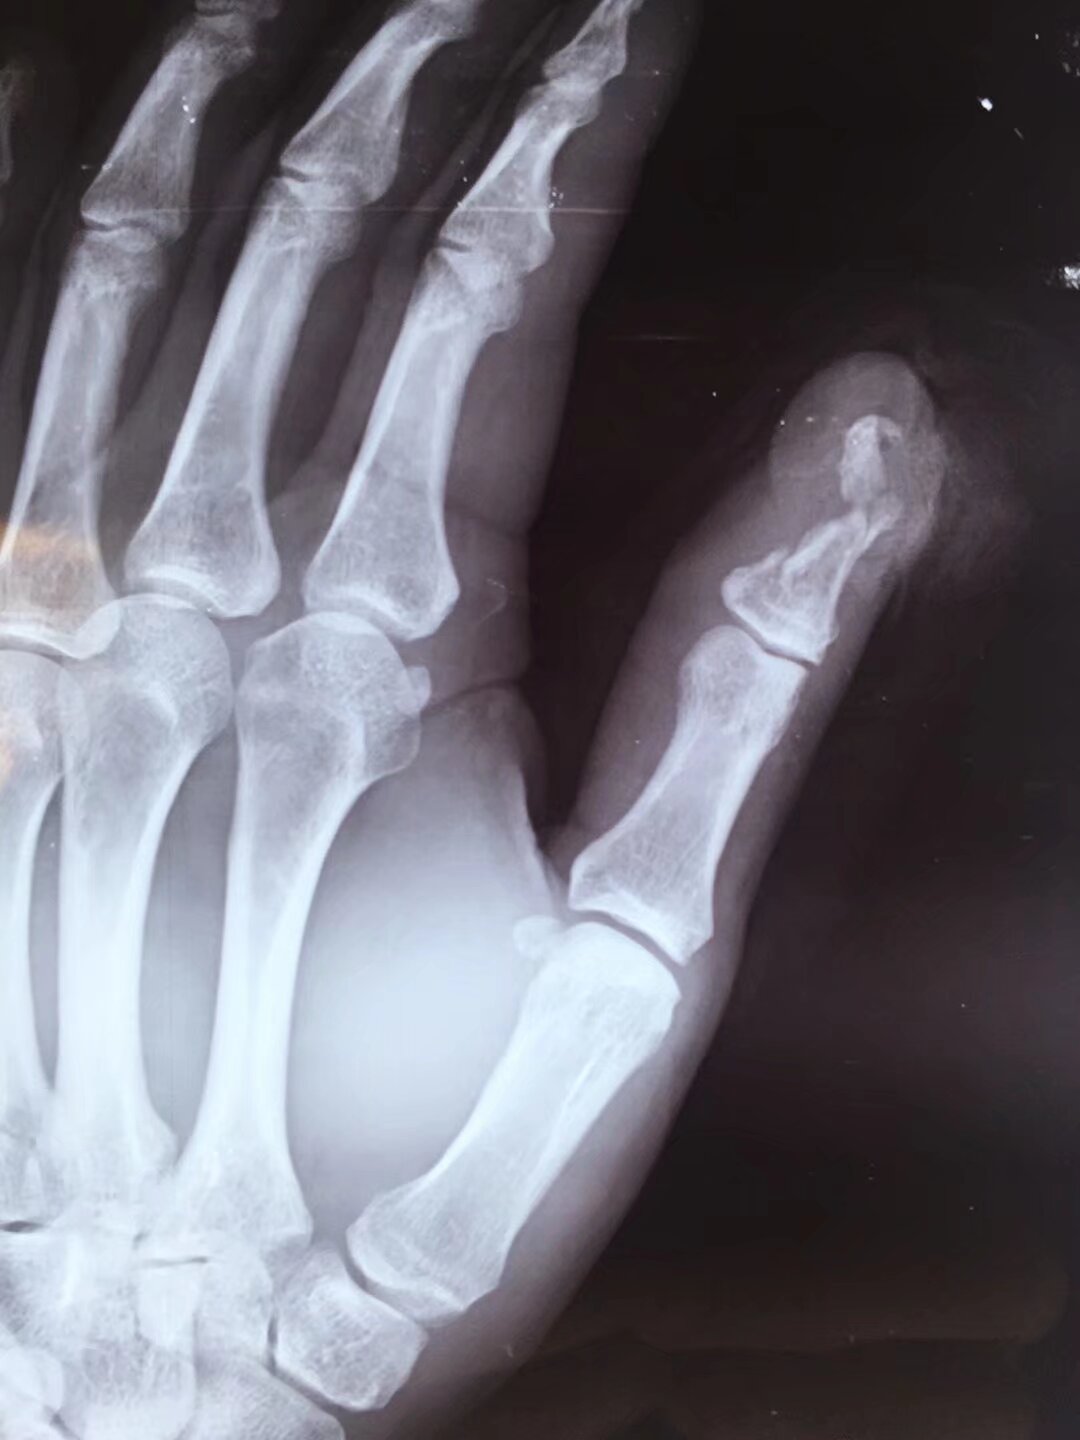

指骨骨折后,克氏针固定是临床常用的治疗方法,尤其适用于手法复位困难或不稳定的骨折,其应用主要体现在以下方面:

2常用固定方式

- 单根克氏针固定:适用于简单横形骨折或斜形骨折,从骨折一端穿入,穿过骨折线至另一端,直接固定断端。

- 交叉克氏针固定:对于斜形、螺旋形或粉碎性骨折,采用两根克氏针交叉穿入骨折端,增加固定稳定性,防止旋转或侧方移位。

- 髓腔内固定:从指骨远端或近端髓腔穿入克氏针,贯穿骨折线,利用髓腔支撑作用固定,适用于长斜形或短缩倾向明显的骨折。